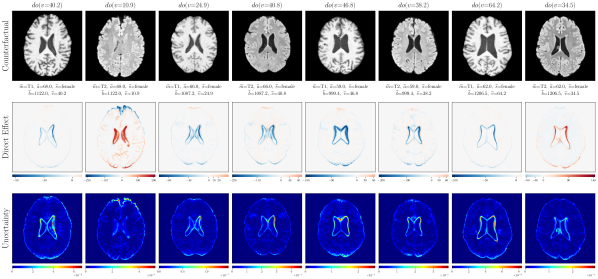

4.3 Chest X-ray Imaging Counterfactuals

We further extend the proposed approach to the MIMIC-CXR dataset (Johnson et al., 2019) to demonstrate our model’s ability to estimate high-fidelity counterfactuals of real chest X-ray images. This is motivated by the need for a better understanding of algorithmic bias and reported subgroup disparities (Bernhardt et al., 2022). We begin with an assumed causal generative process of data involving the following observed variables: age (), sex (), race (), disease (), and chest X-ray image (). Notably, we assume that age causes disease (pleural effusion) which requires inference of discrete counterfactuals from upstream interventions on age. For details on computing discrete counterfactuals and other experiments, please refer to Appendix E. Following the general setup in Section 4.2, we used a scaled-up version of our exogenous prior HVAE for ’s mechanism. We trained for relatively few iterations on MIMIC-CXR; K. The quantitative counterfactual evaluation results from random interventions on each variable are reported in Table 2. We observed significant improvements in counterfactual effectiveness post counterfactual training, particularly for race, age and disease attributes. For extensive visual evaluation results please refer to Appendix E.4.

E.4 Extra results

‘Sex’ counterfactuals

Post counterfactual training:

‘Race’ counterfactuals

‘Age’ counterfactuals

‘Disease’ counterfactuals

Null-Interventions on full SCM